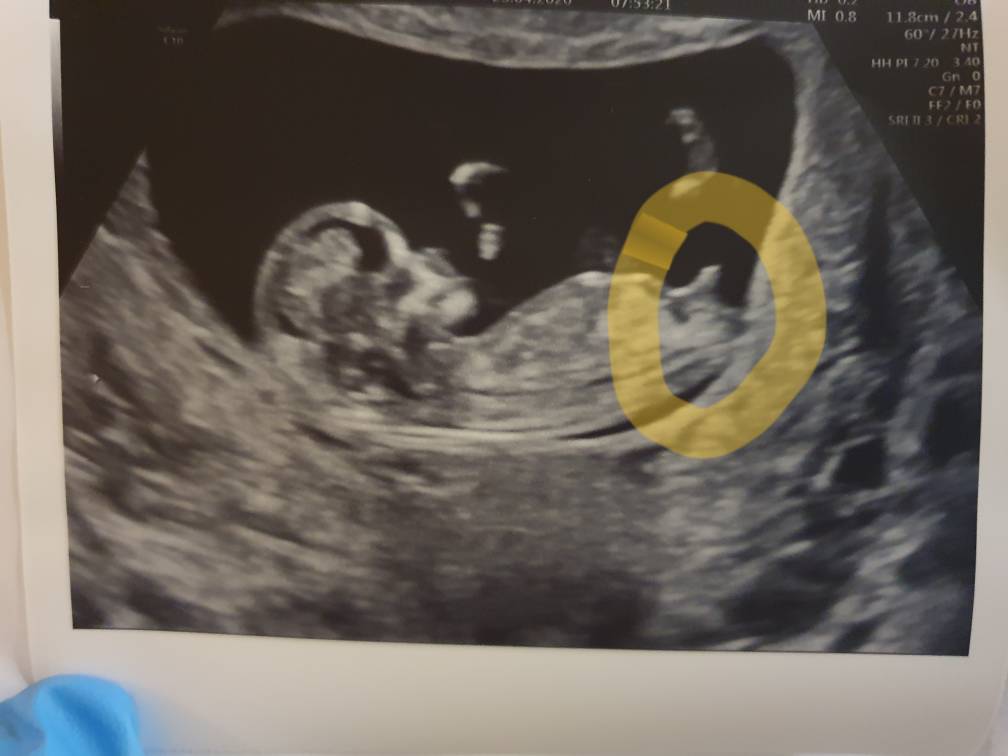

Ja już po usg, jest okjeszcze czekam na pobranie krwi

Tym razem gin też zabawił się w odgadywanie płci i jego zdaniem na 90% chlopak [emoji23][emoji23][emoji23]

Jak się fajnie ruszał maluszek [emoji7] pierwszy synek to był śpioch i zawsze na USG odwrócony był pupa i spała tutaj mlodziak brykal [emoji7]

USG zrobil, bo z pomiarów zamiast 11+4 wyszło 12+1

Zobacz załącznik 1109969

Rzeczywiście na chłopaka wyglada. A masz fotę z pierwszych usg czy pokrywa się z ta Metoda lewo/ prawostronna żeby porównać? Jaki to już człowieczek jest . Tak

Ładnie, wyraźnie widać! Gratuluje wizyty.